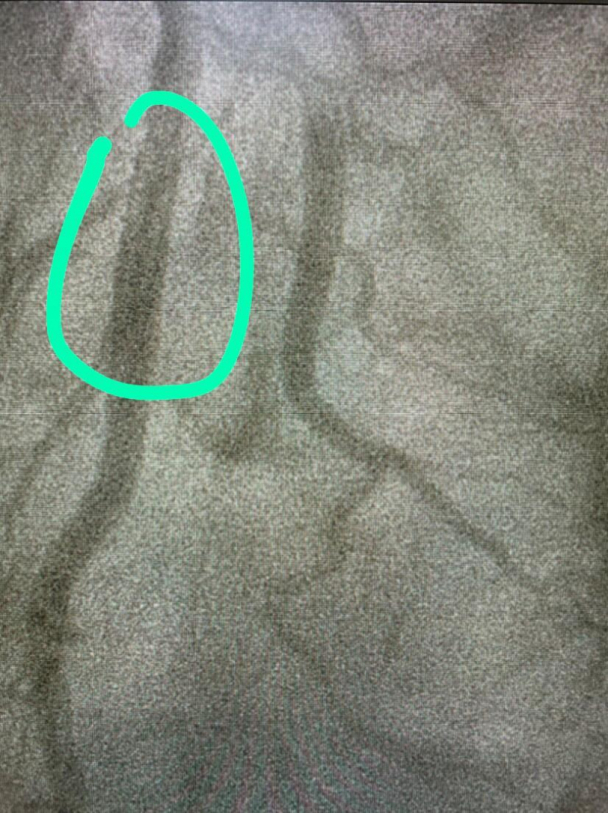

Não demorou muito para a médica concluir o exame e me dar uma má e uma boa noticia ao mesmo tempo: “seu Marco, o senhor tem a artéria coronária esquerda 99% obstruída, mas eu vou desobstruí-la”.

Nada poderia falhar, ou então alguém voltaria em um saco preto. Ali naquela sala a missão era transpassar uma placa de gordura que obstruía 99% da chamada “artéria da viúva” (alguém arriscaria dizer o porquê desse nome!?) e a comandante daquela missão estava ali fazendo o seu melhor.

Antes da intervenção

Antes da intervenção / arquivo Pessoal